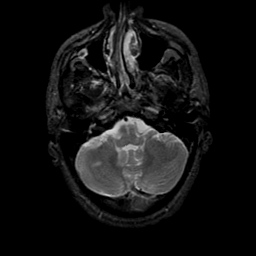

MR Study #9, April 14, 1991 -- Slice #10

[Home][Help][Clinical][Tour 1][Tour 2] Slice 10